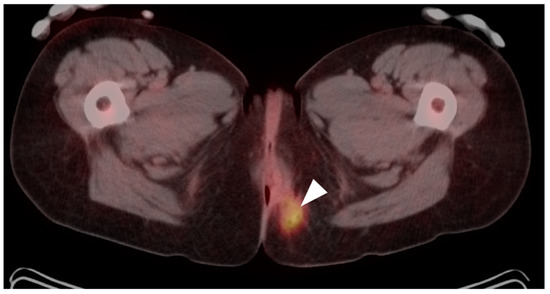

10. Anal Carcinoma